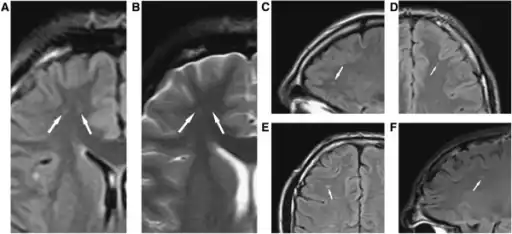

a-f)Diffuse axonal injury on MRI

Diffuse axonal injury after a motorcycle accident. MRI after 3 days: on T1-weighted images the injury is barely visible. On the FLAIR, DWI and T2*-weighted images a small bleed is identifiable.